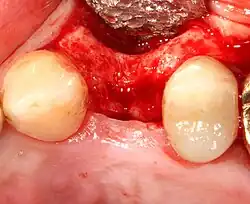

- Soft tissue reflection: An incision is made over the crest of bone, splitting the thicker attached gingiva roughly in half so that the final implant will have a thick band of tissue around it. The edges of tissue, each referred to as a flap, are pushed back to expose the bone. Flapless surgery is an alternate technique, where a small punch of tissue (the diameter of the implant) is removed for implant placement rather than raising flaps.

Additional procedures to augment deficient bone in implant site

For an implant to osseointegrate, it needs to be surrounded by a healthy quantity of bone. In order for it to survive long-term, it needs to have a thick healthy soft tissue (gingiva) envelope around it. It is common for either the bone or soft tissue to be so deficient that the surgeon needs to reconstruct it either before or during implant placement.[50]: 1084 All techniques of augmenting the alveolar bone in preparation for implant placement are invasive and associated with a degree of morbidity.[59]